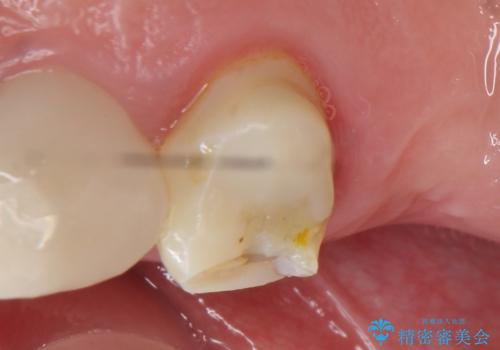

- アメリカの歯科医院にて治療途中の歯の仮歯が割れてしまったので診て欲しいといらっしゃった方の症例です。

しばらくアメリカに戻れそうにないため、当院での治療を希望。土台の築造まで処置は終わっているとのことだったのでオールセラミッククラウンによる補綴のみを行いました。